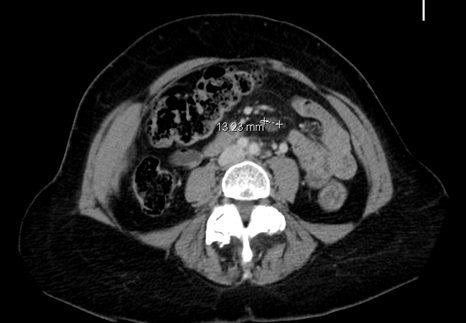

Classement rémission complète avec adénomégalies résiduelles sous- diaphragmatiques non hypermétaboliques

Décision : R-CHOP21 x 8 cycles avec prophylaxie neuro-méningée par 4 PL méthotrexate, en raison de l’IPIaa à 2 et des LDH augmentée. Evaluation par scanner après 4 cycles et par TEP-FDG après 8 cycles.

Classement LNH diffus à grandes cellules B CD20+, stade III, OMS = 1, LDH augmentées soit 2 facteurs selon IPIaa.